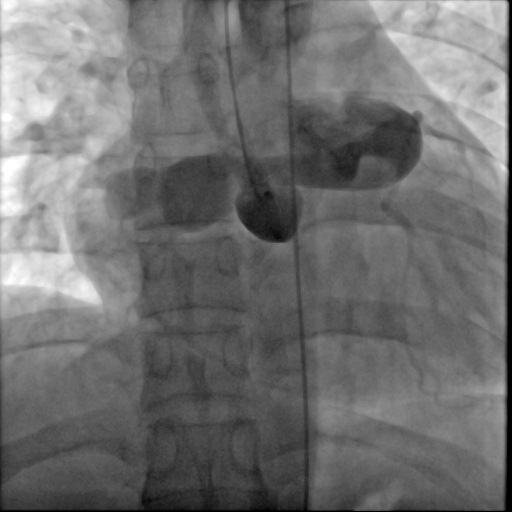

图:患者术后

“我们的治疗方案是在左冠状动脉右房瘘瘘道内放置封堵器,目的就是用封堵器把这个异常的血管通路封闭掉,这种方式创伤小、恢复快,同时也能解决患者的问题。”朱建峰介绍。

术后,患者胸闷、气促、恶心等症状随之消失。进院时患者家属的愁容满面亦随之消失,症状缓解后喜笑颜开的对心血管内科医护团队的辛勤付出和努力表示诚挚的感谢。